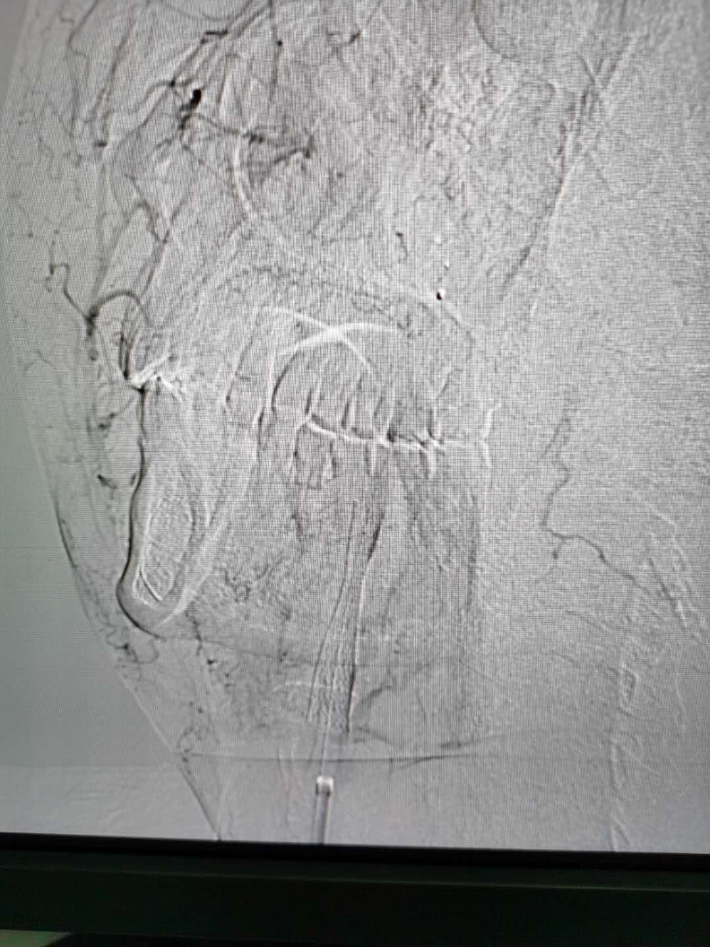

左侧椎动脉起始段重度狭窄及处理后

右侧颈内动脉起始段重度狭窄

球囊扩张及支架植入过程

支架植入后影像

术中及术后情况

手术在局麻下进行,术中患者生命体征稳定,手术顺利完成;术后生命体征稳定,无明显神经缺损症状较重,且患者自诉头晕等不适症状较前明显减轻,记忆力、计算力等高级神经功能较前有所改善,5天后好转出院。